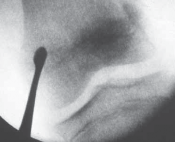

3. Under image intensification control, a 3-mm-wide osteotome is directed through the skin incision to make a longitudinal split in the periosteum–cortex, and the physeal plate is then penetrated to a depth of about 0.5 cm (

TECH FIG 1C,D

).

4. The osteotome is rotated to create a hole in the physis and is then withdrawn.